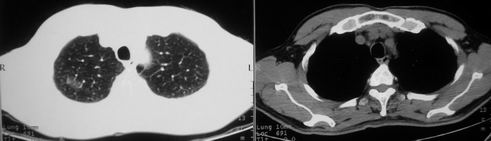

男,62岁,咳血两天。无其他不适。

右肺上叶浅淡密度增高影,考虑炎性病变

像多个结节聚集在一起的病变,且密度较淡  首先考虑为结核吧  建议密切复查

片状磨玻璃影,考虑肺泡出血可能性大,其他不排除,建议hrct

右上磨玻璃样密度影,考虑就是个肺泡出血,别的没有

病灶呈“磨玻璃影”,较薄,周围无卫星灶,很难一口说是肺结核,建议积极治疗后,短期复查!(支持考虑:肺泡出血!)

右肺上叶可见多发磨玻璃状影,符合肺泡内出血表现,严格意义上讲应该是肺泡内积血。引起出血的原因很多,不一定非得结核所致。